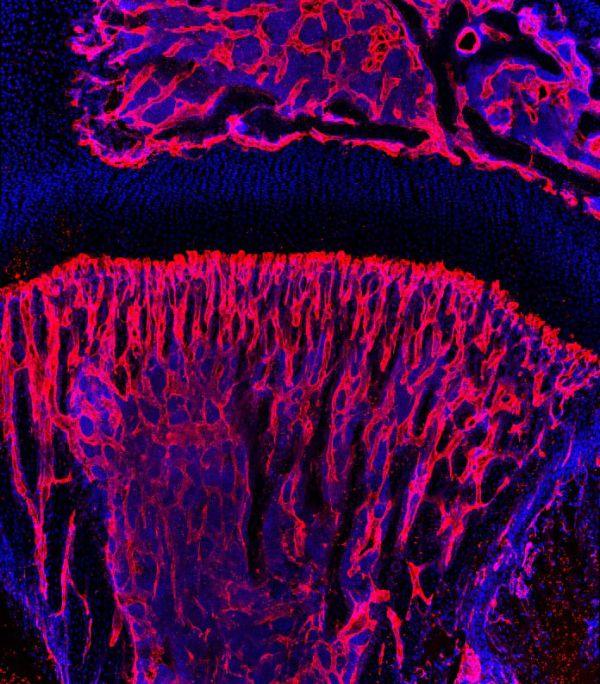

Ein fein verästeltes Netzwerk aus Blutgefäßen versorgt alle Organe des Menschen mit Nährstoffen und entfernt schädliche Stoffwechselprodukte aus den Geweben. Das Wachstum dieses Gefäßsystems ist für alle Entwicklungs- und Heilungsprozesse von größter Bedeutung. Umgekehrt kann unkontrolliertes Blutgefäßwachstum auch Krankheitsprozesse fördern – so wie beispielsweise Hämangiomen, schwammartigen Gefäßwucherungen in der Haut, oder Retinopathien im Auge von Diabetikern und alternden Menschen.

Dr. Rui Benedito, Postdoktorand in Adams Abteilung, konnte jetzt an Mausaugen zeigen, dass Blutgefäße durch Ausschalten des Notch-Signalwegs, eines steuernden Regelkreises, auch ohne die Aktivität von VEGF/VEGFR2 wachsen können. „In einem solchen Fall fördert dann ein weiterer, verwandter Rezeptor namens VEGFR3 die unkontrollierte Vermehrung von Blutgefäßen im Mausauge", erklärt Benedito. VEGFR3 wird durch das Fehlen von „Notch“ in den Gefäßen sehr stark hochgeregelt und ist dann auch ohne Signale aus der Gewebeumgebung aktiv.

Ein fein verästeltes Netzwerk aus Blutgefäßen versorgt alle Organe des Menschen mit Nährstoffen und entfernt schädliche Stoffwechselprodukte aus den Geweben. Das Wachstum dieses Gefäßsystems ist für alle Entwicklungs- und Heilungsprozesse von größter Bedeutung. Umgekehrt kann unkontrolliertes Blutgefäßwachstum auch Krankheitsprozesse fördern – so wie beispielsweise Hämangiomen, schwammartigen Gefäßwucherungen in der Haut, oder Retinopathien im Auge von Diabetikern und alternden Menschen.

Dr. Rui Benedito, Postdoktorand in Adams Abteilung, konnte jetzt an Mausaugen zeigen, dass Blutgefäße durch Ausschalten des Notch-Signalwegs, eines steuernden Regelkreises, auch ohne die Aktivität von VEGF/VEGFR2 wachsen können. „In einem solchen Fall fördert dann ein weiterer, verwandter Rezeptor namens VEGFR3 die unkontrollierte Vermehrung von Blutgefäßen im Mausauge", erklärt Benedito. VEGFR3 wird durch das Fehlen von „Notch“ in den Gefäßen sehr stark hochgeregelt und ist dann auch ohne Signale aus der Gewebeumgebung aktiv.